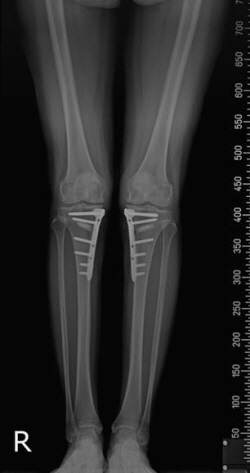

휜다리교정술(절골술)로 휜다리를 교정한 모습

휜다리내반슬은 수술적 치료를 통해 근본적인 원인을 해결하는 게 중요하다. 정밀검사를 통해 다리의 변형된 정도를 정확히 파악하고, 무릎관절 아래 뼈를 반듯하게 교정해주는 ‘절골술’이다. 휜 다리를 반듯하게 펴줌으로써 무릎 안쪽에만 지속됐던 신체 하중을 분산시킬 수 있다. 자기관절을 보존할 수 있는 치료이기 때문에 부담이 덜하고, 휜다리 교정과 무릎통증까지 함께 개서할 수 있다.

허동범 과장은 “절골술 치료는 무릎관절 자체를 수술하는 게 아니라 무릎 아래 뼈를 반듯하게 교정한다”며 “연골손상이 많이 진행되지 않은 50~60대 휜다리 환자들에게 유용하며, 무릎내측만 손상된 환자에서 치료효과가 높다”고 설명했다.